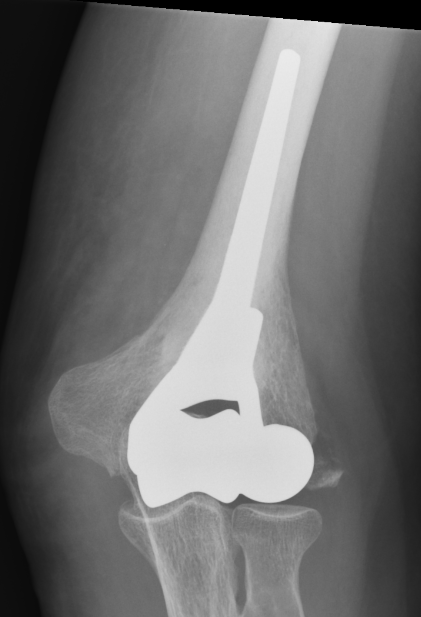

Comminuted coronal shear fracture in elderly patient treated with distal humerus replacement